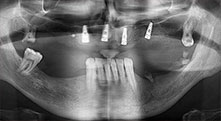

Bratu: We routinely use the instruments for harvesting bone blocks and splitting alveolar ridges. We also use the Piezomed B6/B7 for osteotomy of impacted teeth and removing failed implants. All indications that require deep, clean cuts.

Could you describe briefly, for example, your procedure for mobilizing bone blocks for transplantation?

Bratu: We prefer to harvest bone from the external oblique ridge of the posterior mandible, not from the interforaminal region. After the soft-tissue incision, we use the new saws to define the amount of bone to harvest. With this approach, we also use them for the entire preparation in almost 80% of cases. We may also use other piezo instruments and then at the end a chisel to mobilize the block. We find that this is a very effective surgical technique.

Bratu: We like to use the sandwich technique for augmentation in the lateral mandible. A bone cover is prepared with the piezo saw and the crestal fragment is fixed with microscrews. We place a mixture of autologous bone and xenogenic bone replacement material in between. This works very reliably. You should always ensure sufficiently dimensioned vertical cuts when splitting the alveolar ridge in the mandible. Otherwise the bone may fracture easily.

Bratu: I consider piezo surgery a great leap forward in oral surgery. The technique makes bone preparation safer and easier. Little bone is lost, for example in extractions. This is very important in the aesthetic zone, particularly if immediate implantation is planned. Piezo surgery is also safer for soft tissue: injuries to membranes in the sinus are basically history, as are nerve injuries when bone blocks are being harvested. Data indicating reduced postoperative swelling and pain are also available. Piezo surgery is also ideal for preparation of sinus septa. And last but not least, our patients benefit from the atraumatic nature of this technology.